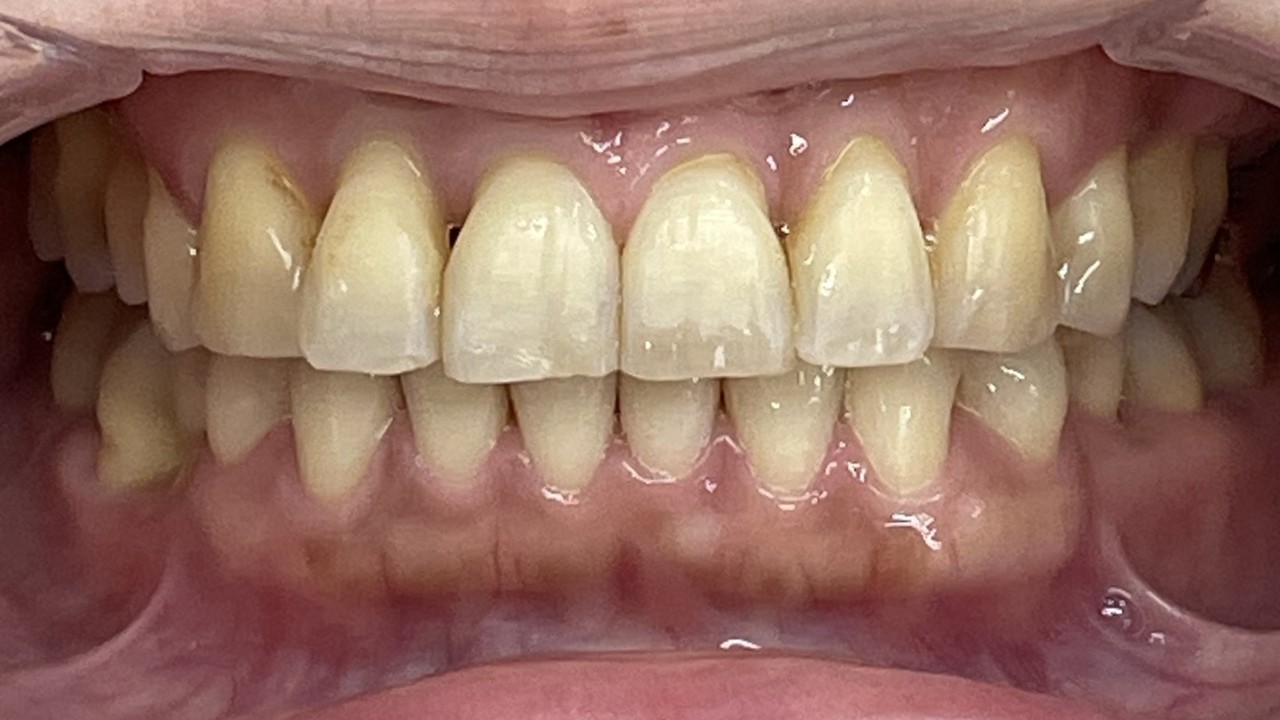

Before

After

矯正の種類 / invisalign GO

年齢・性別 / 50代女性

主訴  /  叢生 交叉咬合

治療期間 / 17ヶ月

費用 / 簡易検査 5,000円(税別) 精密検査 30,000円(税別)

両額マウスピース 450,000円(税別)  両額リテイナー料 60,000円(税別)

※マウスピース交換時別途調節料3,000円(税別)

副作用 / 口内炎・歯の移動に伴う痛み・知覚過敏 ※数日で収まる場合が多いです

リスク / 後戻り防止の為、夜のみマウスピースで保定を指示